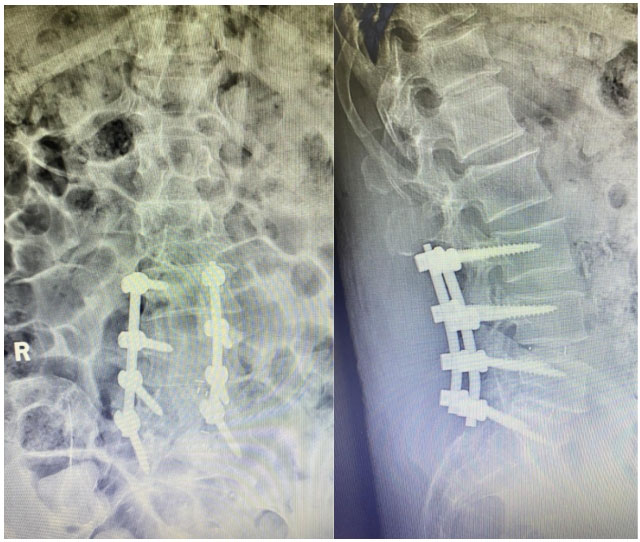

患者是一位66岁的男性,多年来深受下肢瘫痪和大小便失禁的病痛折磨。他曾辗转多家医院,尝试了针灸、理疗、药物等多种治疗方法,但症状不仅没有缓解,反而逐渐加重,最终导致下肢瘫痪和大小便失禁。绝望之际,患者经亲戚介绍来到巨野县中医医院骨伤一科就诊。 术前MR检查 骨伤一科学科带头人杨建安主任医师凭借丰富的临床经验,揭开了病痛的神秘面纱——一种罕见的“特发性椎管内硬膜外脂肪增多症”,这种病症是由于椎管内脂肪组织病理性增生,压迫马尾及神经根所致,常被误诊或漏诊。好发于男性,胸段及腰骶段。硬膜外脂肪增多症常见的病因多与长期摄入外源性甾体类激素、激素异常疾病、肥胖症等有关。 杨建安主任医师介绍,正常人的椎管内含有少量脂肪组织,但该患者的腰骶椎管内脂肪组织异常增多,对神经产生明显压迫,导致下肢瘫痪和大小便失禁。明确病因、完善术前检查并与患者及家属充分沟通后,决定为患者实施常规手术治疗,助他摆脱病痛折磨。手术过程顺利,术后患者恢复良好。 为了帮助患者尽快康复,骨伤一科护士长于凌带领护理团队为患者制定了详细的康复计划,每日督促并鼓励患者进行康复训练。在医护人员的悉心照料和患者及家属积极配合下,患者恢复良好,家属对治疗结果十分满意。 术后DR复查 巨野县中医医院骨伤一科始终致力于攻克疑难病症,以精湛的医疗技术和专业的护理服务为患者带来健康与希望,也展现了医院骨伤科在疑难病症诊疗方面的绝对实力。